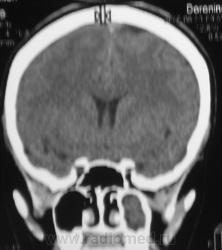

ППН. Клиника гайморита.

Да, эксудативный левосторонний гайморит, в данной случае следует исключать одонтогенную природу, что более вероятно, вообще на данный момент на всех программных обеспечениях МСКТ, имеется мультипланарная программа с мощью которой все 2 ряда зубов как на ладони, с её помощью  удубнее оценивать состояние альвеолярных бухт, другое дело включена ли она в пакет приобреоенных программ.

Все-таки, гаймароэтмоидит: имеется содержимое в левых клетках решетчатого лабиринта. А почему одонтогенный? Зубы внедрены в пазухи с обеих сторон, оценить состояние периапикальных мягких тканей слева из-за жидкости не предсталяется возможным.

Но изменения корней зубов или пролабирование пломбировочного материала-возможно оценить, конечно не поданным сканам, а на рабочей станции, поэтому я только предпологаю, что возможно это одонтогенной природы.